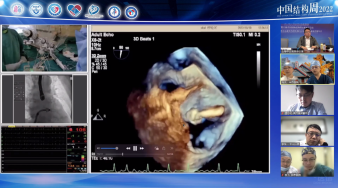

超声描述:

主动脉瓣增厚,回声增强,瓣叶钙化,开放轻度受限,关闭不拢,主动脉瓣环内径21mm;

二尖瓣人工机械瓣,开放正常,瓣周未见异常回声;

尖瓣瓣尖增厚,开放好,关闭不拢;

CDFI:二尖瓣人工瓣未见明显瓣周反流;

主动脉瓣反流,彩束面积72cm²,

三尖瓣反流,彩束面积13.7cm²,估测肺动脉收缩压53mmHg。